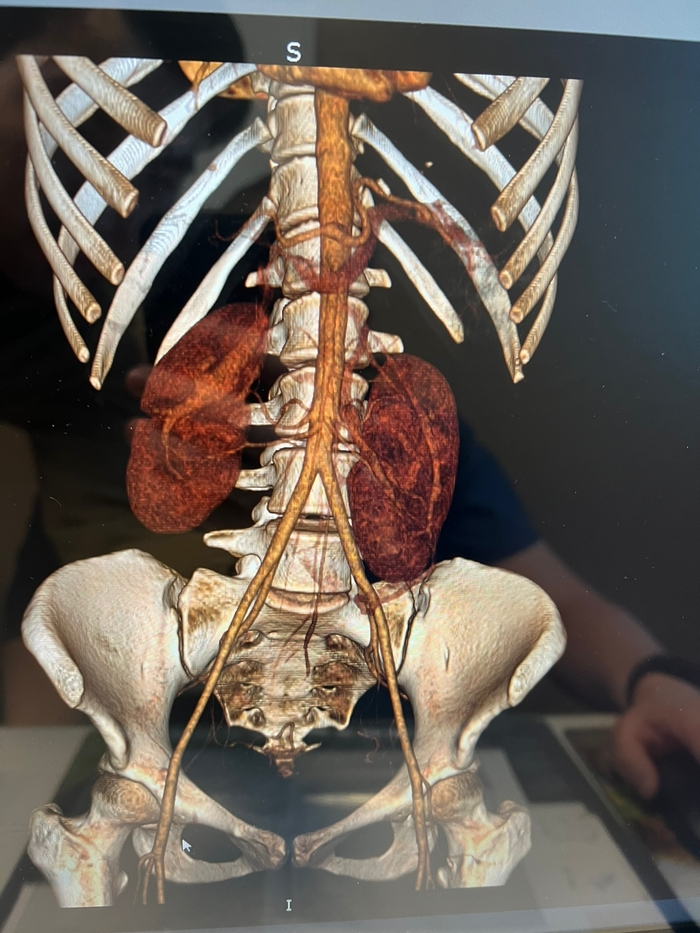

Такое состояние привело меня в Саратов, в педиатрическое отделение УКБ Миротворцева. На основании уросцинтиграфии и компьютерной томографии с контрастом был поставлен истинный диагноз: "Пояснично-подвздошная дистопия обеих почек, ротация левой почки. Гипоплазия левой почки. Вторичный пиелонефрит с потерей функции почек". С 3 до 10 лет функция почек стремительно падала, исследование 2010 года:

КТ контроль через пол года после операции: